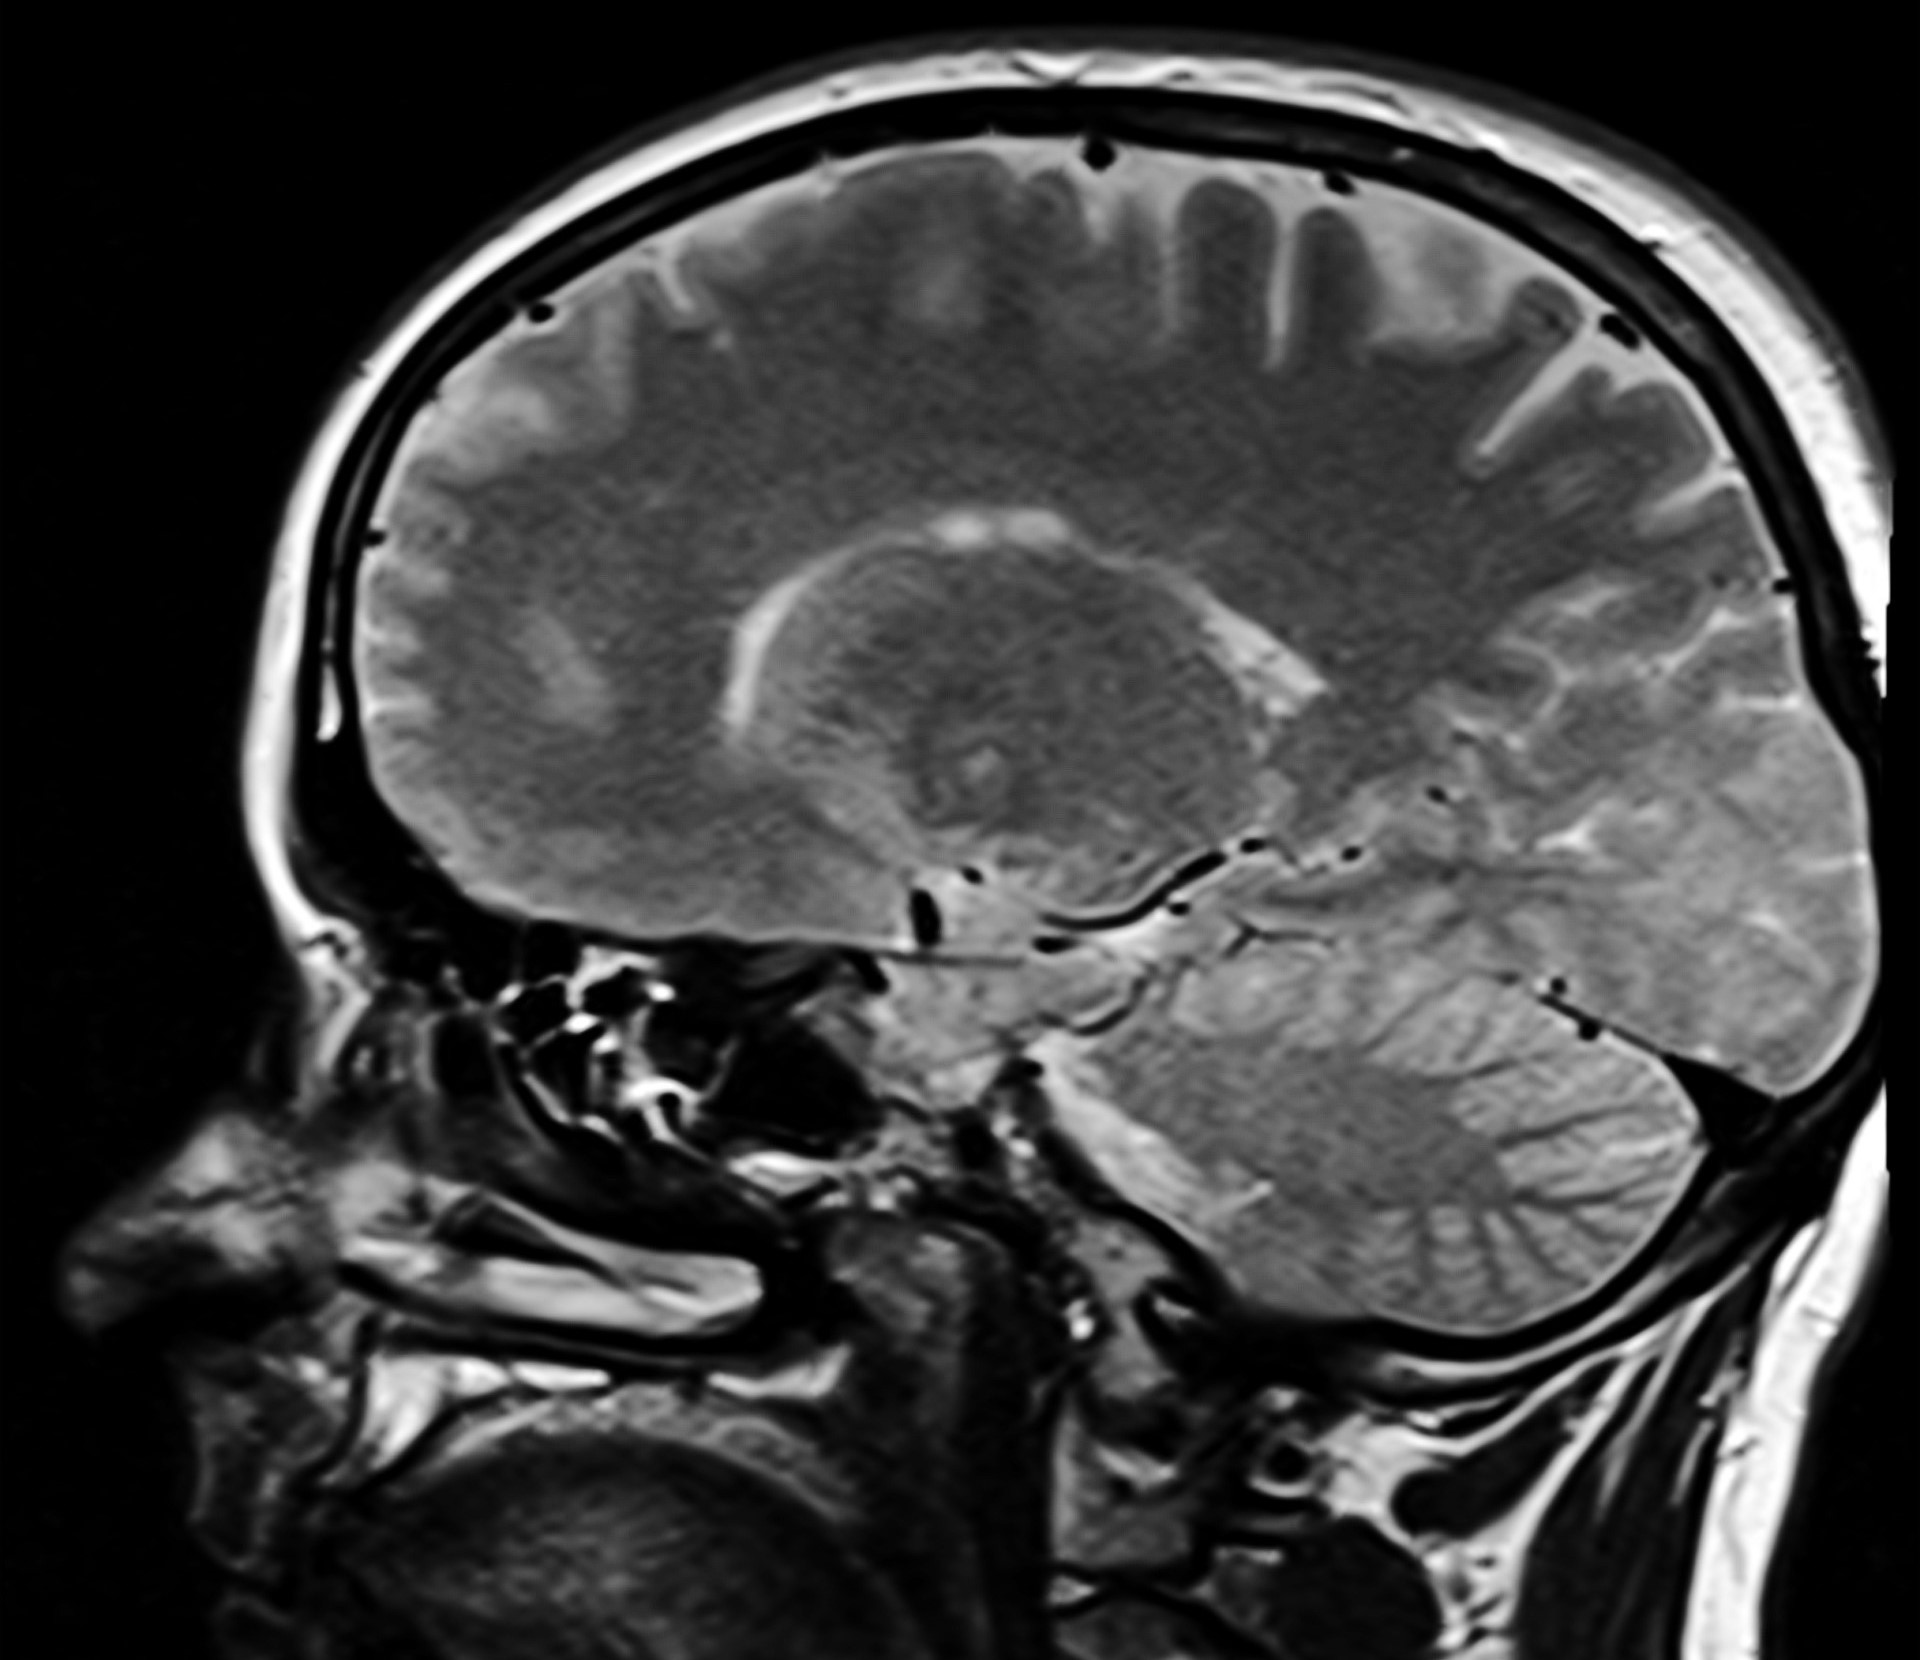

U zdravom mozgu tau protein održava stabilnost živčanih stanica i omogućuje njihovu komunikaciju – što je važno za pamćenje i normalno funkcioniranje mozga.

No kod Alzheimerove bolesti, tau se kemijski mijenja u oblik poznat kao p-tau217. Taj promijenjeni protein se nakuplja unutar stanica i stvara spletove koji ometaju njihovu funkciju, što vodi do gubitka pamćenja i drugih simptoma bolesti.

Ovakav obrazac upućuje na to da p-tau217 ima ključnu ulogu u ranom razvoju mozga, osobito u regijama koje upravljaju kretanjem i osjetilima, a sazrijevaju vrlo rano u životu. Umjesto da šteti, čini se da ovaj protein zapravo pomaže u stvaranju novih neuronskih mreža.